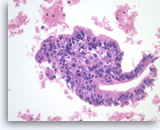

Ductal adenocarcinoma #1,

Pancreas FNA, Direct Smear.

At a higher magnification, the tumor cells are large and pleomorphic and have an unpredictable orientation to each other.

40X